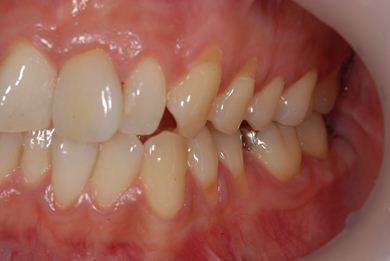

インプラントの症例写真 IMPLANT

インプラント治療+セラミック治療

| 治療内容 | インプラント1本、メタルボンドセラミッククラウン1本、オールセラミッククラウン2本(オールセラミック用土台2本) | ||||||||||||||||||||||||||||||||

| 治療期間 | 1年6ヶ月 |